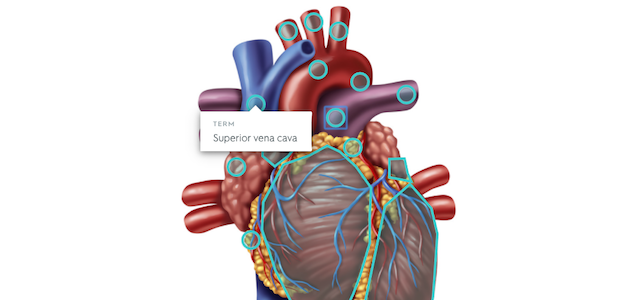

Diagrams allows students to annotate images, maps and other graphics with information, helping them to study efficiently and interactively.